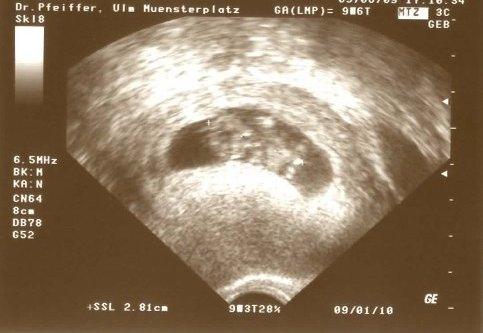

Hallo ihr Lieben! Melde mich auch mal wieder! Mir ging es in letzter Zeit echt nicht so gut, da war mir (fast) gar nicht nach Schreiben zumute Auch heute war ich wieder total müüüüüüüüüüde und der Kreislauf war im aber jetzt bin ich total HAPPY Hatte heute FA-Termin nach unendlichen 4 Wochen. Ich hatte sooooooo einen Schiss das was mit dem Pümelchen ist, aber er/sie ist TOPFIT Ganz schön groß für seine/ihre jungen Tage (2,8 cm), Herz bumpert, Ärmchen und Beinchen wachsen.... ALLES OK. ET soll 09.01.10 sein Ich hoffe ihr freut euch ein bißchen mit mir, auch wenn's euch bestimmt schwer fällt, ihr armen (Mens-)Geplagten. Aber glaubt mir, bei euch ist es auch bald soweit!!! Fühlt euch gedrückt! Steffi

Bild zu Mich mal wieder meld... mit Bild :) - Kinderwunsch - was tun, um schwanger zu werden?